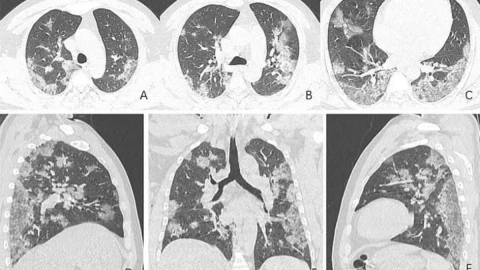

Коронавирустан көз жұмған қытайлық азаматтардың рентген суреттері арқылы мамандар аурудың өкпеге қалай әсер ететіндігін көрсетті, деп хабарлайды Stan.kz ақпарат агенттігі.

44 жастағы Қытай тұрғынының өкпесіне жасалған рентген мен компьютерлік томографияның суреттері оның ағзасында қандай өзгерістер болғандығын көрсеткен. Дәрігерлердің айтуларынша, коронавирусқа шалдыққандардың өкпесі рентген суреттері ЖРВИ мен MERS жұқтырғандардікіне ұқсайтынын аңғартқан.

Мамандар көз жұмған азаматтың Уханьда балық базарында саудагер болып жұмыс істегенін айтады. Суреттерде азаматтың өкпесінің төменгі жағында ірі-ірі қара дақтар байқалады. Бұған қоса өкпеде әлдебір сұйықтықтың бар екендігі расталыпты. Солтүстік Американың радиологиялық қауымдастығы таратқан суреттерде әлгі сұйықтықтың уақыт өте келе көлемі ұлғайғаны аңғарылады.

54 жастағы Уханьда коронавирус жұқтырған әйелдің өкпесінде де дәл осындай өзгерістер байқалыпты.

Ал ауруға шалдыққан 45 жастағы азаматшаның өкпесінде ақ дақтар пайда болған.